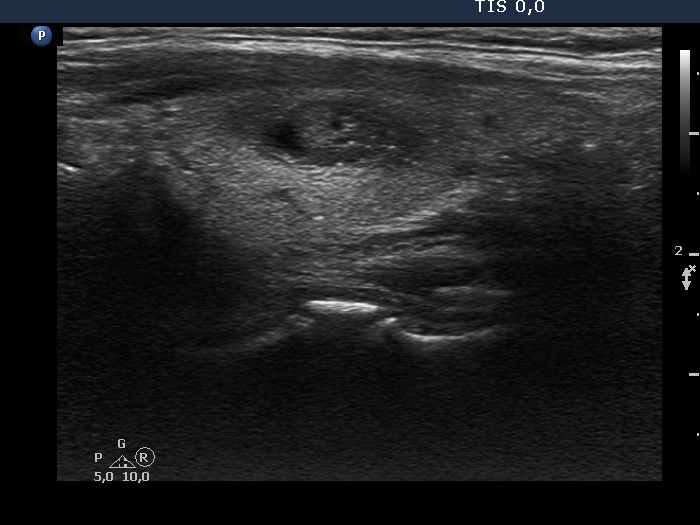

Benign cystic-colloid goiter (cytological diagnosis) - case 1473

The synchronous presence of bright granules and lines are ultrasound presentations of the connective tissue.